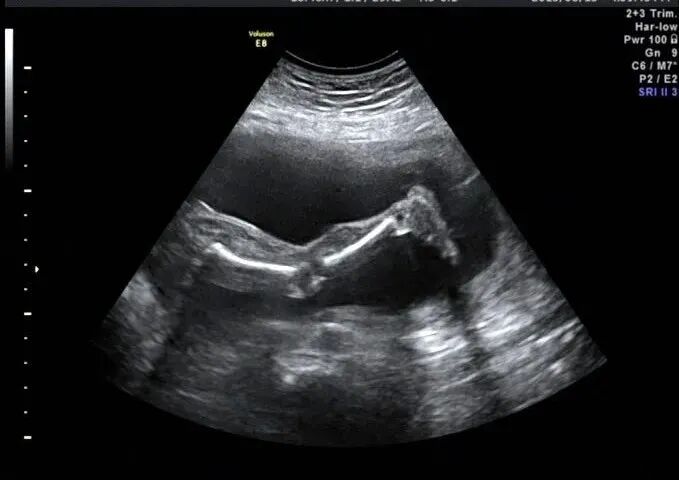

再看脚也不对劲,马上启动三维超声,下图是三维超声表现

手脚都有问题,呈龙虾爪样,非常典型的手裂足裂,胎儿父母没有啥疾病